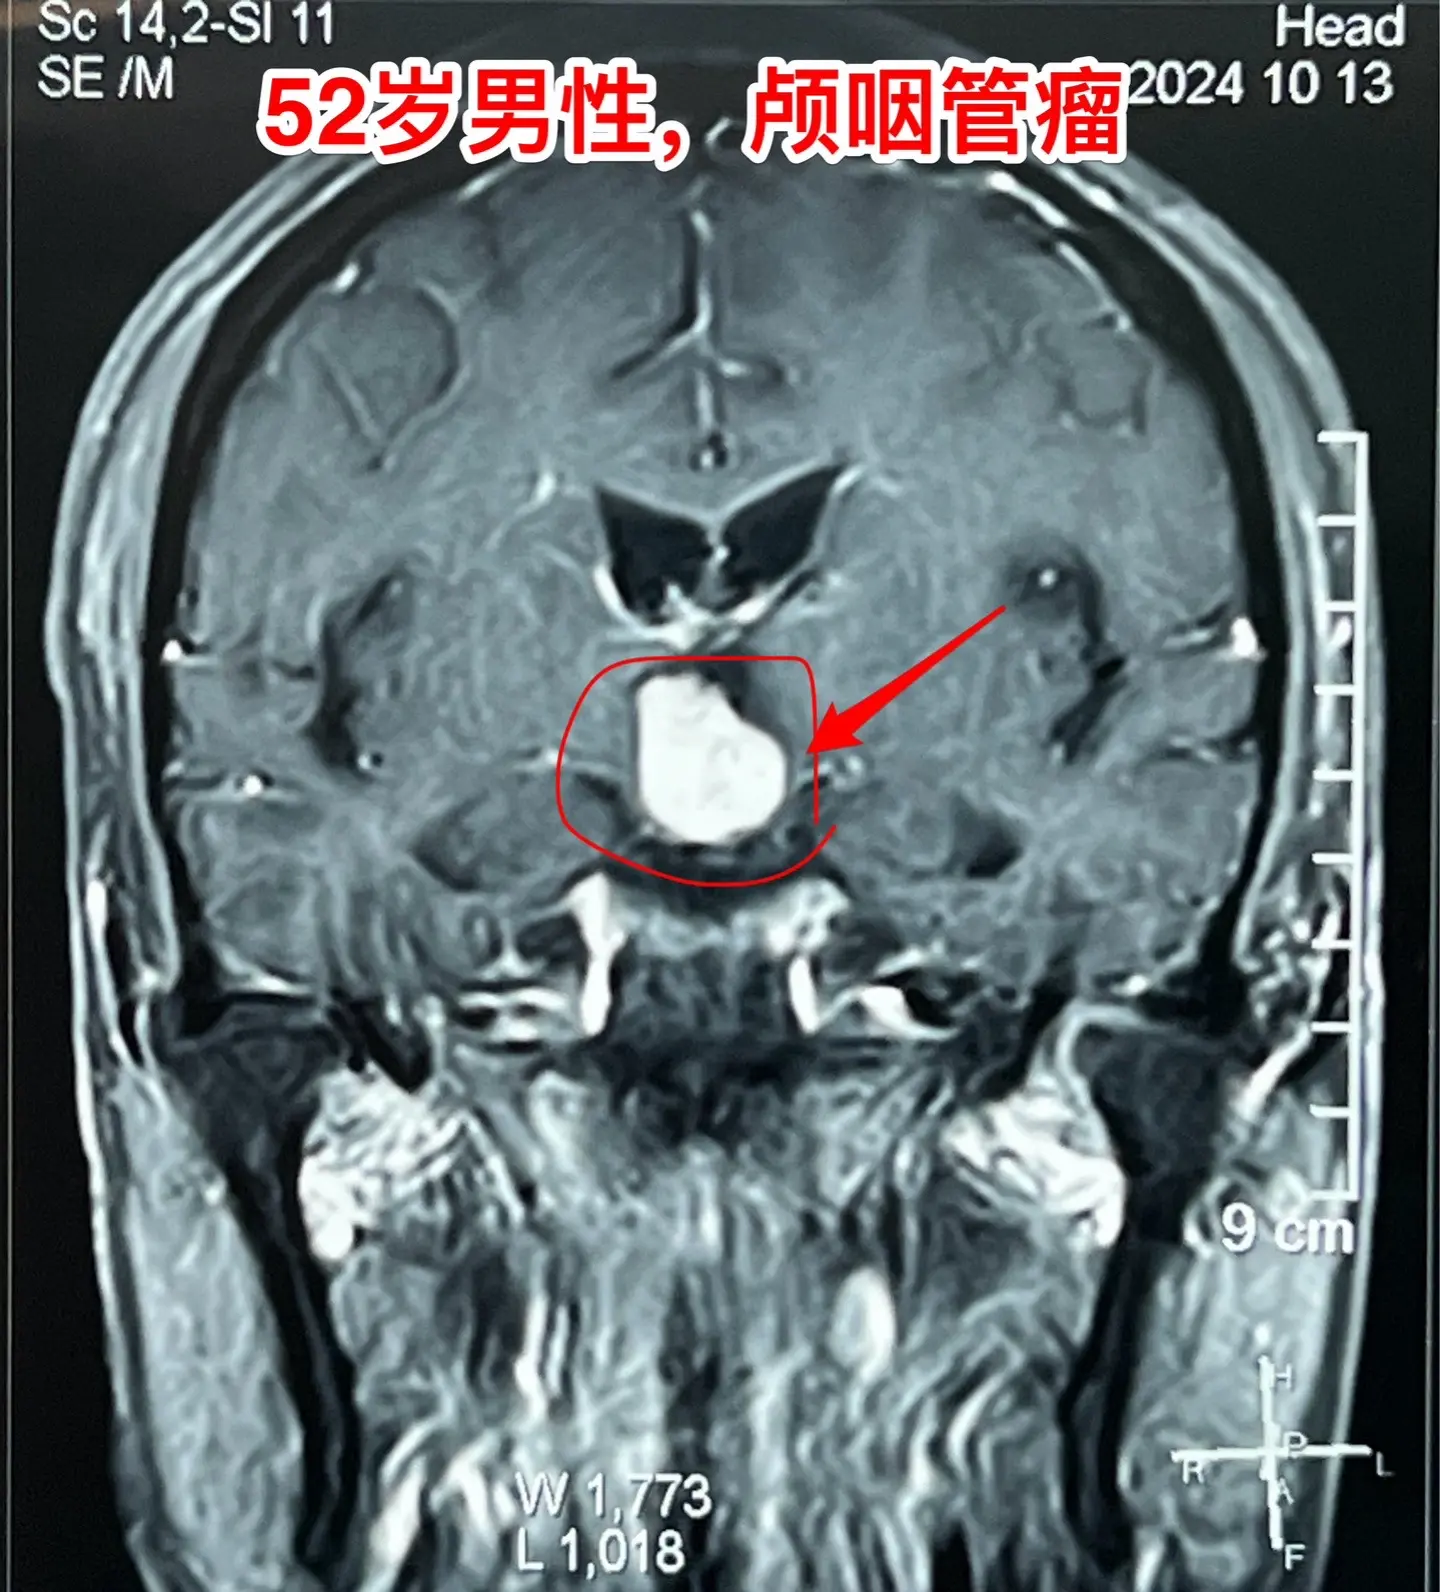

乳头型颅咽管瘤。52岁的重庆市男性,因为头痛到医院检查磁共振,居然发现脑部有个颅咽管瘤,典型的乳头型颅咽管瘤。CT显示肿瘤没有钙化,基本就是一个实性肿瘤。 患者的女儿是重庆市某医院的手术室护士。通过重庆三博脑科医院的医生找到我,来北京三博脑科医院作手术。10月18日顺利切除肿瘤,垂体柄保留约50%。 针对乳头型颅咽管瘤,第一选择还是手术切除,而不是首选靶向药(有的患者对手术感到害怕,希望用药物治疗颅咽管瘤)。